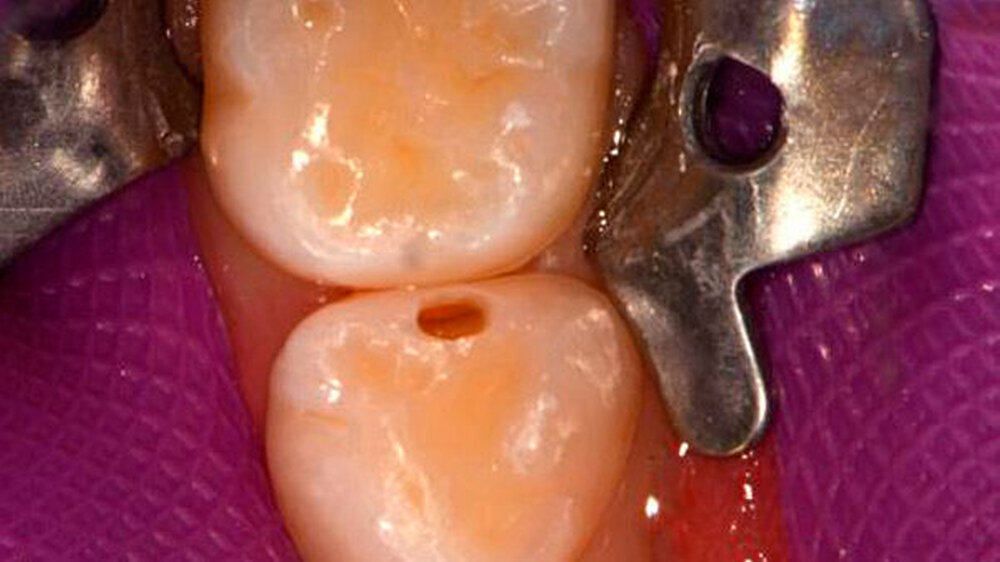

Zuerst ist fast immer der Vierer distal betroffen, dann folgt der Fünfer mesial. Milchzähne haben durchschnittlich nur eine Schmelzdicke von einem Millimeter, der Schmelz am Vierer distal ist noch dünner, das heißt noch anfälliger. Der Kontaktpunkt 4/5 bildet sich erst in der Gebrauchsphase des Milchgebisses, wobei er zusätzlich häufig flächiger wird. Die anderen Kontaktpunkte im Milchgebiss lösen sich durch die physiologische Lückenbildung eher auf, das Kontaktpunktkariesrisiko sinkt also.